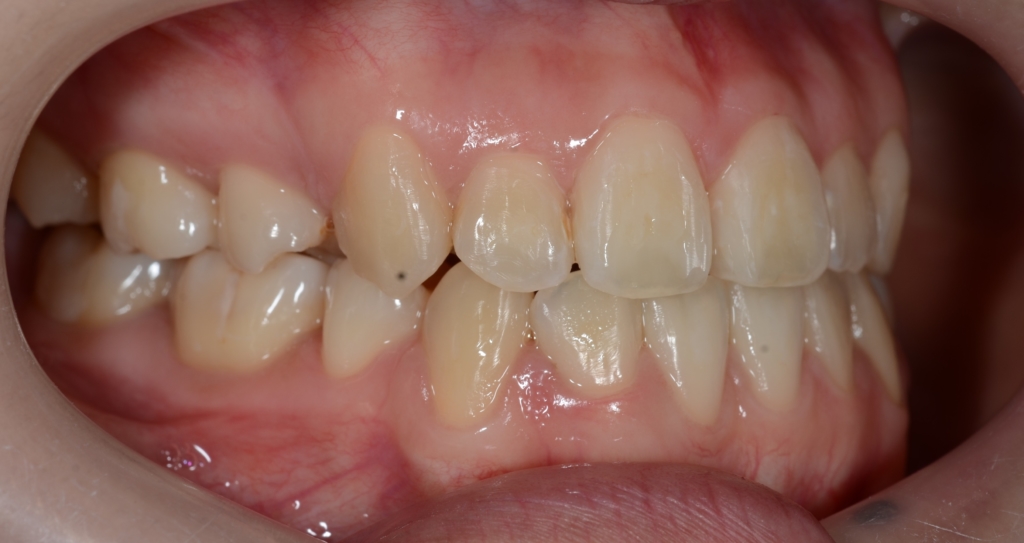

【Before】

#1.顎と歯の不調和による叢生

(前歯部の反対咬合を伴う)

#2.骨格的に下顎前突(受け口)傾向

と診断しました。